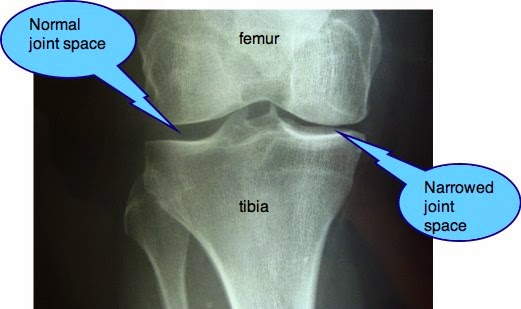

Knee joint with labels. Alila Medical Media | Knee joint, basic labels | Medical illustration Image size: 39.1 Mpixels (112 MB uncompressed) - 6250x6250 pixels (20.8x20.8 in / 52.9x52.9 cm at 300 ppi) A Labeled Diagram of the Knee With an Insight into Its Working Labeled Diagram of the Knee Joint Knee joint is one of the most important hinge joints of our body. Its complexity and its efficiency is the best example of God's creation. The anatomy of the knee consists of bones, muscles, nerves, cartilages, tendons and ligaments. All these parts combine and work together. shoulder joint with labels - Scottsdale Joint Center The Scottsdale Joint Center is in Arizona - Call us at 480-994-1149. Dr. Stuart Kozinn is an orthopedic surgeon in private practice in Scottsdale. Knee x-ray - labeling questions | Radiology Case | Radiopaedia.org Normal X-ray Knee - Frontal (with labels) Annotated image Frontal Knee Frontal 1. Femoral shaft 2. Patella 3. Base of patella 4. Apex of patella 5. Adductor tubercle of femur 6. Medial epicondyle of femur 7. Medial condyle of femur 8. Lateral epicondyle of femur 9. Lateral condyle of femur 10. Groove for popliteus 11. Intercondylar fossa 12.